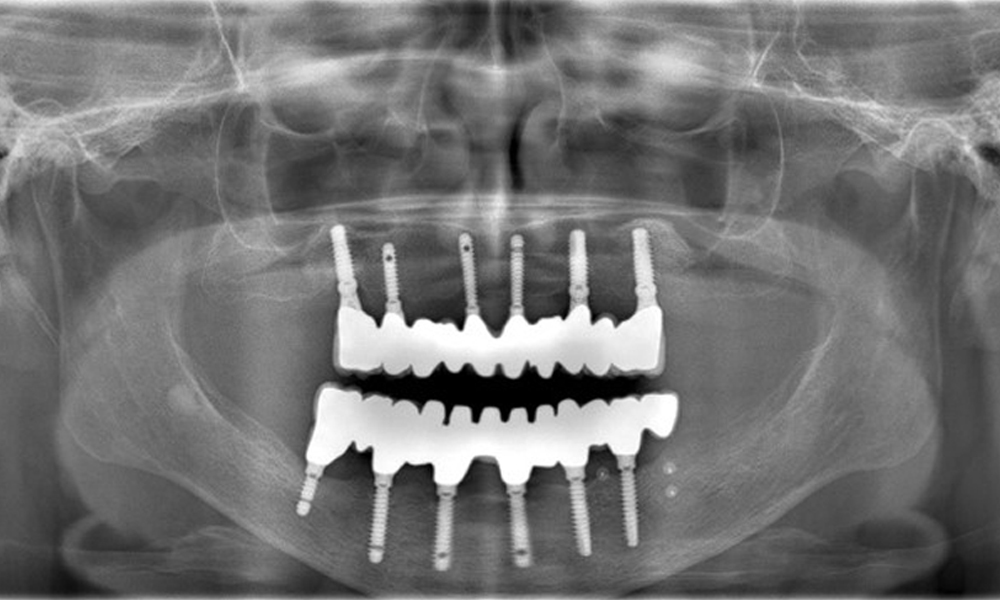

A 74-year-old patient presents for a consultation. The anamnesis shows that the patient has well-controlled hypertension and is taking Lixiana. Additionally, the patient had a kidney carcinoma in 2020. The patient’s lifestyle is unremarkable. She has no natural teeth left and has six implants in both the upper and lower jaws, which are fitted with crowns or bridges. Current findings show no peri-implant mucositis or peri-implantitis; however, there are occasional minor bleeding at the implant sites.

Provisions: Implants in regions 011, 013, 015, 021, 023, 025, 031, 033, 035, 042, 044, 046

The use of Lixiana represents a risk factor; therefore, the complication risk is considered moderate. The oral health is stable and good. To detect potential peri-implantitis early, probing depths (PD) should be measured during follow-up appointments. If there is an increase in PD at the implant compared to the baseline, combined with diffuse bleeding, radiographic diagnostics (e.g., dental X-rays) should be pursued.

The peri-implant situation is currently stable. Due to the complexity of the superstructures, the patient has a moderate risk of development and a low risk of progression for peri-implant diseases.